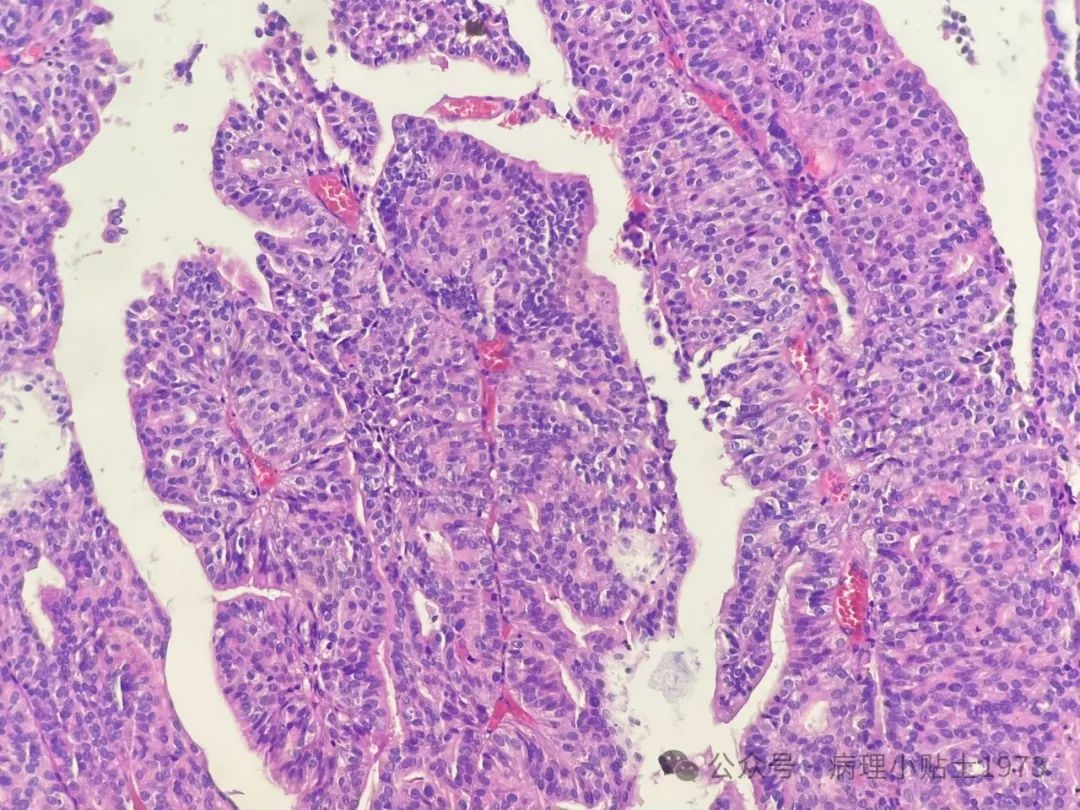

- 识别尿路上皮癌成分: 尽管存在显著腺性分化,但仔细观察仍能找到经典的复层排列的尿路上皮癌成分。这是区别于原发性膀胱腺癌的关键。尿路上皮癌可伴有多种变异型(异向分化),包括鳞状分化、腺样分化等。

- 腺性分化的意义: 伴有腺样分化的尿路上皮肿瘤通常提示高级别的可能性更大。需要与良性的腺性膀胱炎或囊性膀胱炎鉴别。

- 肿瘤分级的挑战: 本病例的肿瘤细胞极性轻度紊乱,核异型性为轻到中度,部分区域可见核仁,凋亡易见。免疫组化显示p16和CK20弥漫表达(常提示高级别),Ki67指数也较高。这使得按照传统的WHO 2004/2022标准将其归类为低级别还是高级别存在争议。